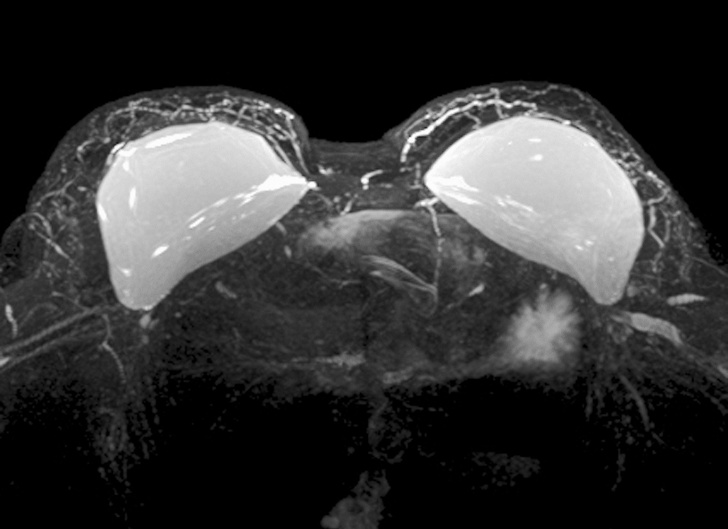

在磁共振下,硅胶乳房一览无余。